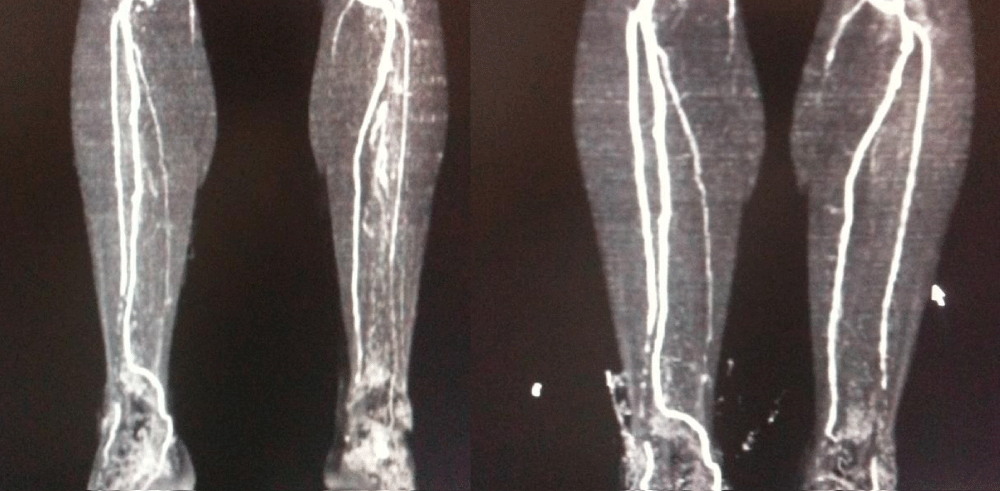

Download Image

Figure 4: Exemplary CT angiographic images preoperatively and at postoperative month 6.

Figure 5: Exemplary CT angiographic images preoperatively and at postoperative month 6.

Following intra-arterial + intramuscular stem cell transplantation, a significant increase in ABI was noted, together with significant growth in pain-free maximum walking distance and mild improvement in skin saturation index. In those with extremity wounds, the wound healing process also appeared to be accelerated. Tomographic angiography at 6 months showed the formation of small new vessels as a result of angiogenesis in one-third of the patients. Of the 8 patients with critical ischemia that could require amputation, major amputation was performed in 2, and minor amputation in 1. The two patients who required major amputation were those who had undergone therapy with stem cells of adipose origin. A patient with a minor amputation had received stem cells of bone marrow origin.